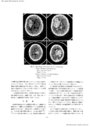

基底核部高血圧性脳出血劇症型の検討